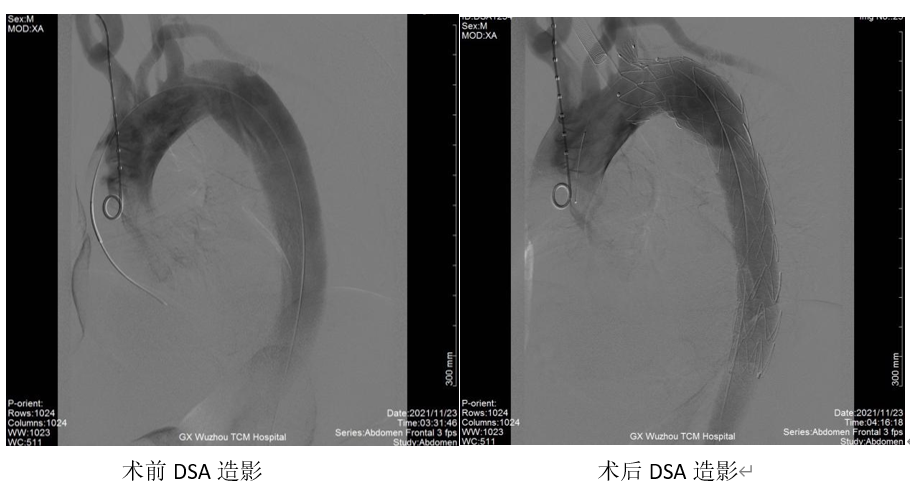

近期,刘某因运动后出现胸痛来我院就诊,急查CTA检查结果显示:主动脉夹层DeBakeyⅢB型。收住我院血管介入科,入院后予降血压、降心率及止痛对症治疗,因病情危重,后转入重症医学科。在住院完善检查同时,我院血管介入科主任、副主任医师陈庆航、傅建斌副主任医师、郭文震主治医师经过全面、慎密的评估与讨论,决定对患者施行主动脉造影及主动脉覆膜支架腔内隔绝术,手术安排在入院后第二天晚上,经过4个小时的手术,成功置入主动脉覆膜支架。